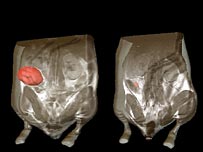

Imagens mostram que tumor encolheu em organismo de rato

Imagens mostram que um tumor encolheu em um organismo de rato

Experiências com animais de laboratório mostraram que mesmo que reativado brevemente, o gene reduz drasticamente o tamanho dos tumores, em alguns casos em até 100%.

Os pesquisadores usaram ratos de laboratório resultantes de manipulação genética que tinham o gene p53 desativado.

Mas eles também incluíram um "interruptor" que permitia que os pesquisadores reativassem o p53 depois que os tumores se desenvolveram.